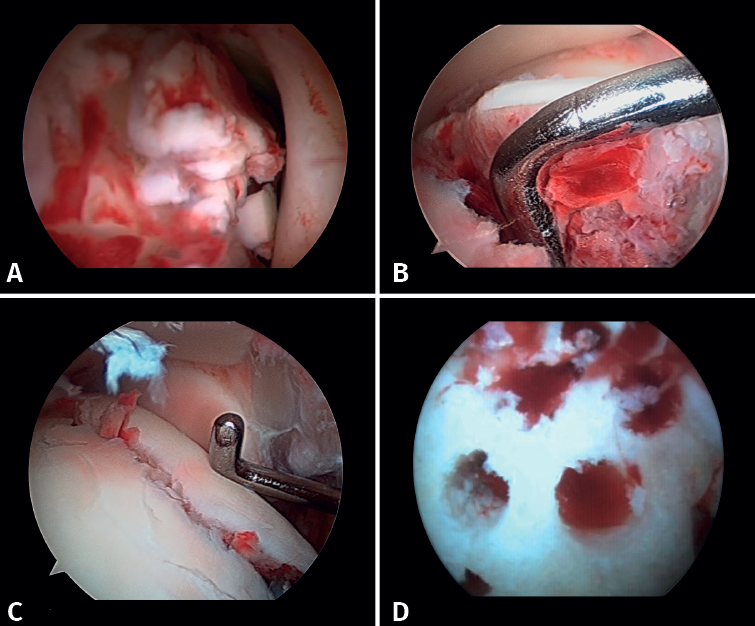

2. Open reduction and internal fixation of the lateral and/or medial malleolus

Arthroscopy assists ORIF in evaluating the congruence of the joint surface. It is especially useful for reduction of the medial malleolus. The malreduction rate in medial malleolus fractures is 22.2-32.6%(15,16). Initial arthroscopy allows us to determine whether tibial malleolus reduction can be performed in an open or closed manner. In cases with significant displacement, open synthesis is chosen, always maintaining arthroscopic control during the procedure to ensure precise reduction and avoid rotation of the distal fragment (Figure 4).

If the deltoid ligament injury involves only the anterior part, arthroscopic reinsertion can be made using resorbable implants. If deltoid ligament disinsertion is complete, open reinsertion is preferred, because of the difficulty of placing the implants in the posterior malleolus and the risk of neurovascular injury (Figure 5).

- Arthroscopy can help avoid overcorrection of the syndesmosis, which is highly arthrogenic(5,24) (Figure 6).

Figure 6. A: syndesmosis injury; B: control of reduction to avoid overcorrection; C: intraoperative control of correct reduction of the fibula at the incisura.